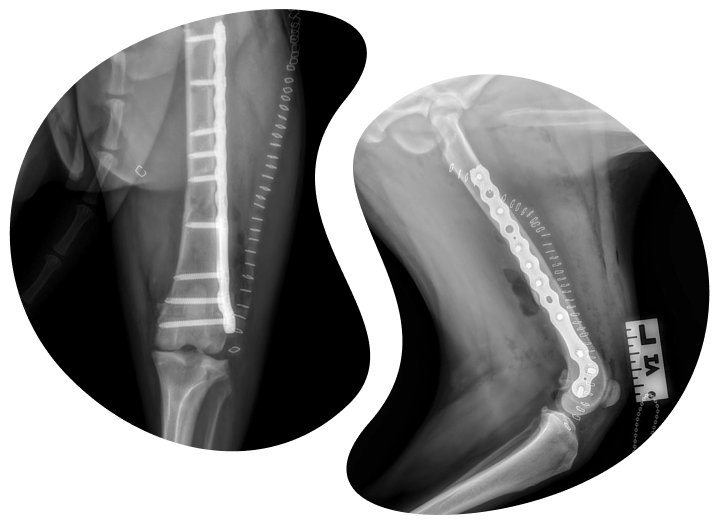

The Titanium Standard: We exclusively use high-grade titanium alloy implants for ALL orthopedic procedures (including TPLO and fracture repair) for superior biocompatibility, strength, and reduced infection risk.

We specialize in bringing advanced, board-certified veterinary surgery directly to your pet’s primary care clinic. Our most popular mobile services include complex orthopedics—like TPLO for cruciate ligament repair and fracture stabilization—as well as a wide range of soft tissue procedures to offer your pet expert care in a stress-free, familiar environment.